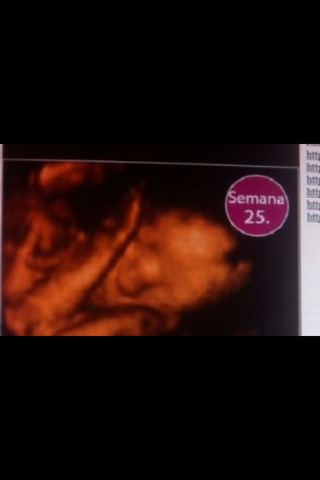

Sus medidas son 20 cm y 340g

Las uñas, parpados y cejas son visibles, solo faltan las pestañas

El sistema límbico del bebé esta en desarrollo,se encargan de sentimientos y emociones